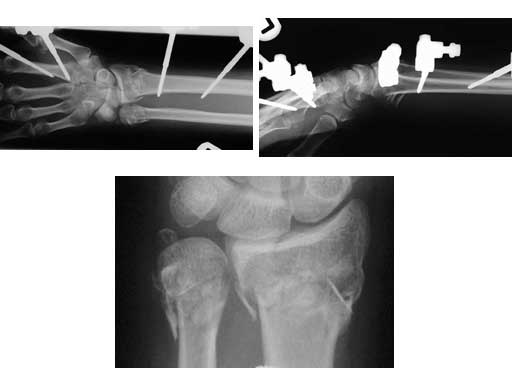

A 48-year-old female had an accident while on vacation. Local temporary treatment was performed with a bridging external fixator and definitive treatment with a plate 2 weeks postinjury.

Fig 1ac Preoperative x-rays (AP, lateral, close-up).

Fig 2ab AP and lateral x-rays 4 months after ORIF of a segmental unstable fracture of the distal ulna including basistyloid avulsion and extraarticular fracture of the distal radius.